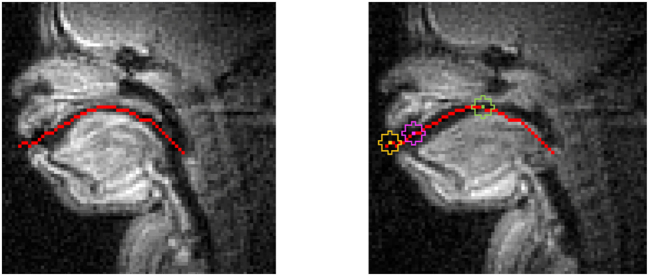

目前的项目对垂直喉部动作和多姿态复杂音段(如弹出音和内含音)中的咽喉间定时稳定性进行了运动学检查,这些音段可能具有对其发音实现至关重要的特定时间目标。本研究利用豪萨语非喉音和喉音辅音的实时核磁共振成像(rtMRI)语音生成数据,阐明了片段内口腔收缩和垂直喉部动作之间的语音时序,以及这种酝酿间时序在不同前音语境中实现语音对比和过程中所起的作用。结果表明,垂直喉部动作在弹出音的发音中比喉音的发音中幅度更大,但内弹音和喉音辅音的区别不在于垂直喉部动作的幅度,而在于其口腔收缩和垂直喉部动作之间的妊辰模式。此外,口腔动作和非口腔动作(喉垂直动作)之间的酝酿时间稳定性/可变性在喷出辅音、内隐辅音和喉音辅音之间也有所不同,其中喷出辅音的时间滞后最稳定,其次分别是内隐辅音和喉音辅音。最后,研究结果表明了对比性语言 "分子"--这里指的是具有多种手势的语段大小的语音复合体--如何与语音中的短语语境相互作用,从而在参与的手势之间形成不同的时间组织,并尊重构成一个语段的这些手势之间相对时间的稳定性。

The current project undertakes a kinematic examination of vertical larynx actions and intergestural timing stability within multi-gesture complex segments such as ejectives and implosives that may possess specific temporal goals critical to their articulatory realization. Using real-time MRI (rtMRI) speech production data from Hausa non-pulmonic and pulmonic consonants, this study illuminates speech timing between oral constriction and vertical larynx actions within segments and the role this intergestural timing plays in realizing phonological contrasts and processes in varying prosodic contexts. Results suggest that vertical larynx actions have greater magnitude in the production of ejectives compared to their pulmonic counterparts, but implosives and pulmonic consonants are differentiated not by vertical larynx magnitude but by the intergestural timing patterns between their oral and vertical larynx gestures. Moreover, intergestural timing stability/variability between oral and non-oral (vertical larynx) actions differ among ejectives, implosives, and pulmonic consonants, with ejectives having the most stable temporal lags, followed by implosives and pulmonic consonants, respectively. Lastly, the findings show how contrastive linguistic 'molecules' - here, segment-sized phonological complexes with multiple gestures - interact with phrasal context in speech in such a way that it variably shapes temporal organization between participating gestures as well as respecting stability in relative timing between such gestures comprising a segment.